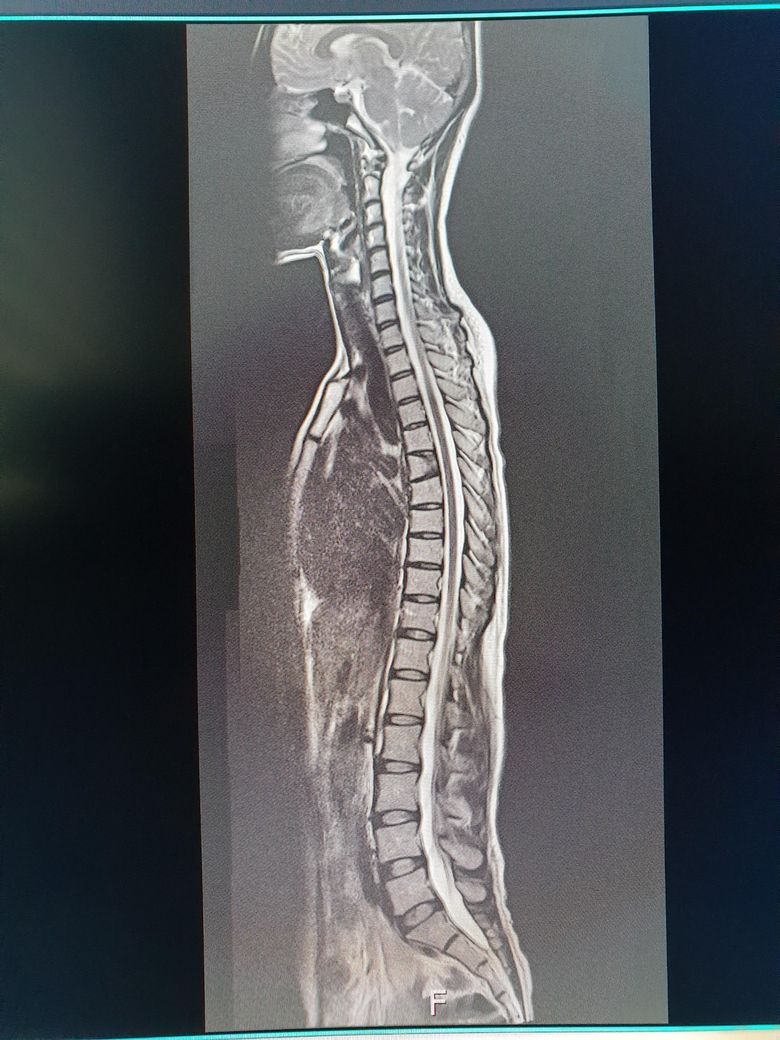

척추mri에서 모양이 다른 흉추뼈 한개가 골절됐던걸까요?

1년전에 mri찍은적이 있었는데요 흉추쪽에 뼈 모양이 하나가 이상한걸 알게됐는데 골절됐었던걸까요?? 평소에는

요추쪽이 항상 통증이있긴한데 참을수있을정도로만 아프지만 위쪽에 뼈가 깨진것처럼된건 mri찍고 처음 알았거든요 나중에 나이들면 문제가 있을지도 궁금합니다

MRI사진상 정확한 상태 확인하기 어려우나 모양이 다르게 보였다면 압박골절이나 선천적인 변형이 있었을 가능성도 존재하며 압박골절이 발생하면 뼈의 높이가 낮아지거나 찌그러져 보일 수 있으며 일반적으로 골절이 있었던 부위는 시간이 지나면서 뼈가 굳어지지만 형태가 변형된 상태로 남을 수 있습니다.

또는 척추뼈가 선천적인 모양 이상일 수도 있고 흉추 골절이나 변형이 있었따면 나이가 들면서 척추의 후만증이나 또는 흉추의 통증 혹은 요추에 추가부담 또는 골다공증이 있다면 추가적인 골절의 위험도 존재하기는 합니다.

이전에 압박골절이 있었다면 MRI판독지에 이전 압박골절 소견이 있을 것이니 확인해보시는게 좋을 것으로 생각됩니다.

MRI상에 흉추에서 뼈가 이상하게보이는건 전에 외상이나 골다공증으로 인해서 발생한 꽤기형 변형일수있습니다 흉추의 골절이 제대로 치유되지않았다면 나이가 들면서 척추의 정렬이나 통증, 신경압박과같은 문제가생길수있으니 병원에서 추가적인검사를받아보시고 필요한 치료를처방받으시길 바랍니다 감사합니다~

흉추의 뼈 모양이 이상하게 보인다면 과거에 골절이 있었을 가능성이 있습니다. 골절이 치유되면서 뼈의 모양이 변형될 수 있으며 이는 통증과 관련이 있을 수 있습니다. 나이가 들면서 척추 건강에 영향을 줄 수 있어 정기적인 관찰이 필요할 수 있습니다!